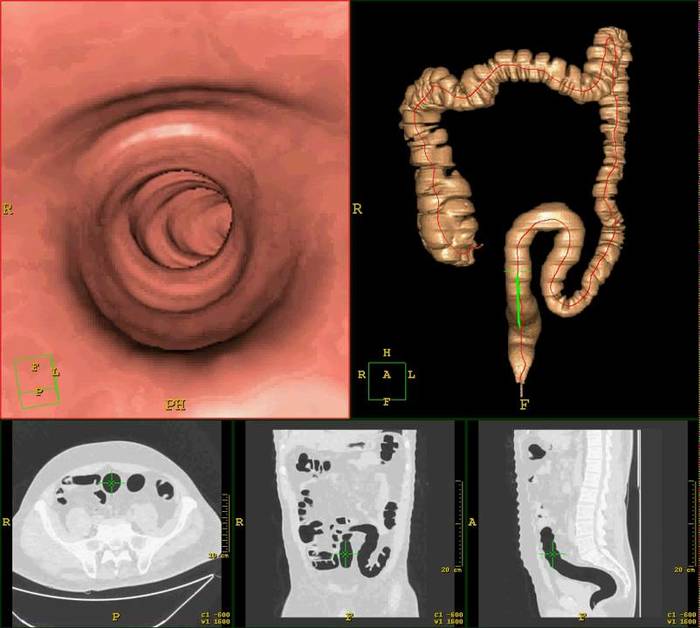

Виртуальная колоноскопия.

"Я такой хитрый, мне не надо делать седацию и никаких неприятных ощущений не будет". Суть - делаем колоноскопию на КТ-аппарате (КТ-колонография). Из плюсов - при умелом диагносте почти как колоноскопия (можно найти полипы от 0,5 см), не нужна седация и не нужен человек с длинным черным шлангом. Из минусов - термоядерная лучевая нагрузка, слабительные всё равно нужно пить, бывает аллергия на контраст, мелкие полипы и дисплазии не видны, биопсию не взять, дороже. Так себе вариант. Для скрининга не очень подходит.